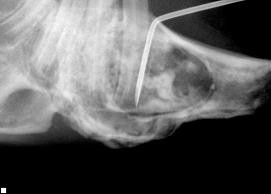

Choroby zebów u królikaW przychodni lekarz obejrzy najpierw głowę i szczękę , siekacze i zgryz można łatwo sprawdzić podnosząc wargi królika. Specjalnym oświetlonym otoskopem (z metalowa końcówką), można ocenić zęby przedtrzonowe oraz miękkie części np. język, policzki. Przy najmniejszym podejrzeniu anomalii cała jama gębowa powinna zostać dokładnie przebadana. Z powodu dużego zagrożenia urazami podczas badania, powinno być one przeprowadzone pod narkoza. Choroby zebów u królika Tylko podczas znieczulenia ogólnego można przeprowadzić szczegółowe badanie wszystkich miejsc w szczęce. Zdjęcie rentgenowskie przy zamkniętej i otwartej szczęce , pozwoli wykryć szczękowo-ortopedyczne problemy. Poza tym można zobaczyć przerost zębów, czy zmian kości i korzeni spowodowanych ropniem.

Innym następstwem dysproporcji pomiędzy przyrostem , a zużyciem zębów jest ich wydłużenie się, w taki sposób, ze zęby trzonowe stykają się cały czas ze sobą. Przez związany z tym nadmierny ucisk, dochodzi do uszkodzenia tkanki w obrębie korzeni zębów trzonowych. To może doprowadzić nawet do przerostu korzeni w przeciwnych kierunkach. Często można zaobserwować przerośnięty korzeń dochodzący aż do gałki ocznej, lub uszkadzający kanalik łzowy. Choroby zebów u królikaW szczęce dolnej za to można wyczuć twarde lub miękkie pogrubienia pod spodem pyszczka, które rozwijają się w stany zapalne kości lub ropnie. Dlatego powiększenie gałki ocznej, łzawienie i wyciek z nosa jak i pogrubienia w obrębie szczeki są symptomami, które mogą wskazywać na problemy z zębami. Wady zgryzu u zwierząt domowych charakteryzują się silnym przerostem siekaczy. Krótsza szczeka górna lub dolna jest przyczyna , ze siekacze nie osiągają idealnej pozycji podczas gryzienia, potrzebnej do ścierania krawędzi. Przy prawidłowym zgryzie nierównomierne lub nieprawidłowe ścieranie siekaczy może wskazywać na problematykę zębów trzonowych.